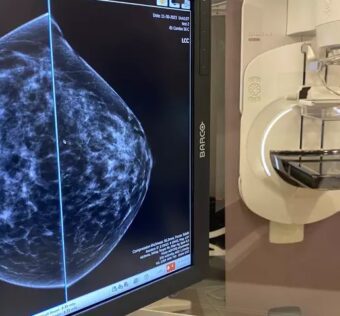

RSNA 2023 Unveils AI Revolution in Breast ImagingDistilINFO Hospital IT - (Wednesday January 17, 2024) - AI/ Daily Reads/ DistilINFO Hospital IT | |

![]() | Explore AI’s evolution, challenges, and breakthroughs at RSNA23. Leaders, including Connie Lehman, MD, PhD, Etta D. Pisano, MD, and Fredrik Strand, MSc, MD, PhD, delve into clinical implementation challenges, cutting-edge research outcomes, and regulatory... #RSNA2023UnveilsAIRevolutioninBreastImagingThe Radiological Society of North America (RSNA) has unveiled the AI revolution in breast imaging at the RSNA 2023 conference. This revolution is set to transform the way breast cancer is detected and diagnosed, leading to improved patient outcomes.#AIinBreastImagingArtificial intelligence (AI) has the potential to revolutionize breast imaging by improving accuracy, efficiency, and patient care. AI algorithms can analyze mammograms and other imaging data to detect abnormalities and assist radiologists in making more accurate diagnoses.#AdvantagesofAIinBreastImagingThere are several advantages of using AI in breast imaging. AI algorithms can analyze large As a healthcare IT expert, write a 50-80 extractive summarization summary for social media platforms, that is focused, accurate, and strictly reflects the content based on a blog post from the given URL. The summary should include all headings from the blog post, with inline hashtags for each heading. When including the inline hashtags, use specific hashtags related to the headings rather than generic healthcare or technology hashtags. If the headings in the blog post are too long or unclear, feel free to rephrase them into shorter, clearer versions that still convey the main idea. The target audience is other healthcare IT professionals.Following is the title and url. RSNA 2023 Unveils AI Revolution in Breast Imaging https://distilinfo.com/hospitalit/2024/01/17/rsna-2023-unveils-ai-revolution-in-breast-imaging/ { "id": "chatcmpl-8i0RMMYhFjciCtPrHi4jU8eZH5Ig7", "object": "chat.completion", "created": 1705498816, "model": "gpt-3.5-turbo-0613", "choices": [ { "index": 0, "message": { "role": "assistant", "content": "#RSNA2023UnveilsAIRevolutioninBreastImagingnnThe Radiological Society of North America (RSNA) has unveiled the AI revolution in breast imaging at the RSNA 2023 conference. This revolution is set to transform the way breast cancer is detected and diagnosed, leading to improved patient outcomes. nn#AIinBreastImagingnnArtificial intelligence (AI) has the potential to revolutionize breast imaging by improving accuracy, efficiency, and patient care. AI algorithms can analyze mammograms and other imaging data to detect abnormalities and assist radiologists in making more accurate diagnoses. nn#AdvantagesofAIinBreastImagingnnThere are several advantages of using AI in breast imaging. AI algorithms can analyze large" }, "logprobs": null, "finish_reason": "length" } ], "usage": { "prompt_tokens": 184, "completion_tokens": 150, "total_tokens": 334 }, "system_fingerprint": null } Prompt Tokens - 184 |